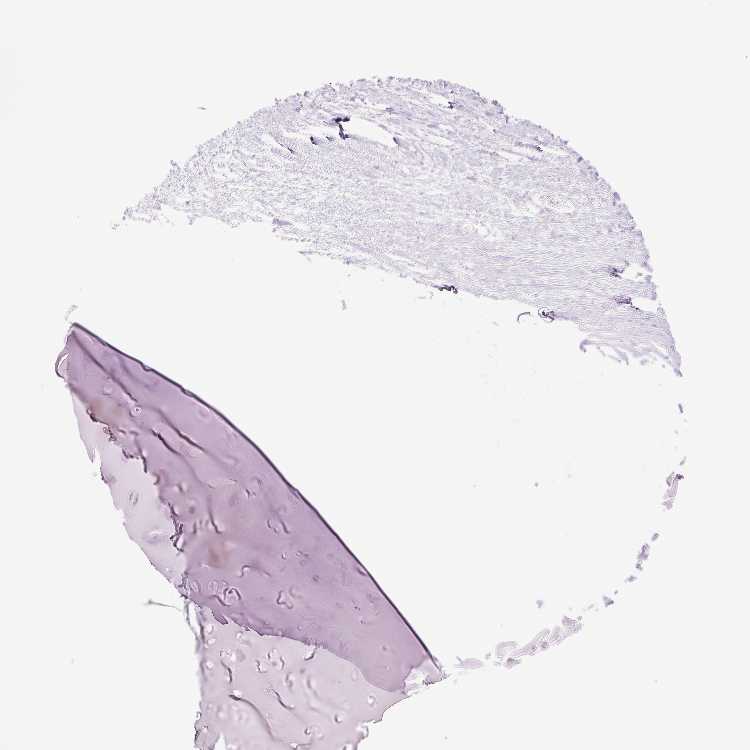

SOFT TISSUE 1 - Antibody stainingi

Antibody staining in the annotated cell types in the current human tissue is reported as not detected, low, medium, or high, based on conventional immunohistochemistry profiling in selected tissues. This score is based on the combination of the staining intensity and fraction of stained cells.

Each image is clickable and will lead to virtual microscopy that enables deeper exploration of all samples and also displays staining intensity scores, fraction scores and subcellular localization as well as patient and tissue information for each sample.

Antibody HPA055721

Chondrocytes Not detected

Fibroblasts Not detected

Peripheral nerve Low